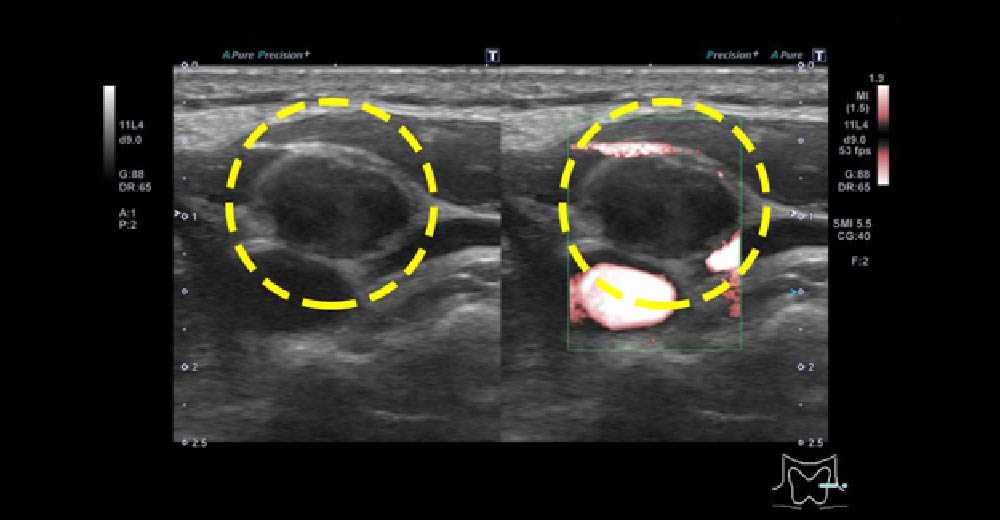

甲状腺がん再発

甲状腺乳頭がん切除術後10年以上の時を経て、左側頸部リンパ節に再発した症例です。

左総頚動脈周囲に、10mmを超えるリンパ節腫脹を認め、再手術に至りました。腫大したリンパ節は辺縁不整・内部不均一で、“丸まった”(縦横比が高い)形です。

術後は定期的な頸部エコーを行いましょう。エコーの時間は、約5-10分程度です。